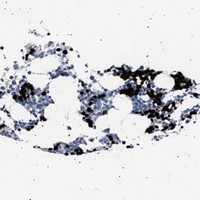

- Experimental details

- Immunohistochemical staining of human bone marrow with HEMGN polyclonal antibody (Cat # PAB21222) shows strong cytoplasmic and nuclear positivity in a subset of bone marrow poietic cells at 1:10-1:20 dilution.

- Validation comment

- Immunohistochemistry (Formalin/PFA-fixed paraffin-embedded sections)